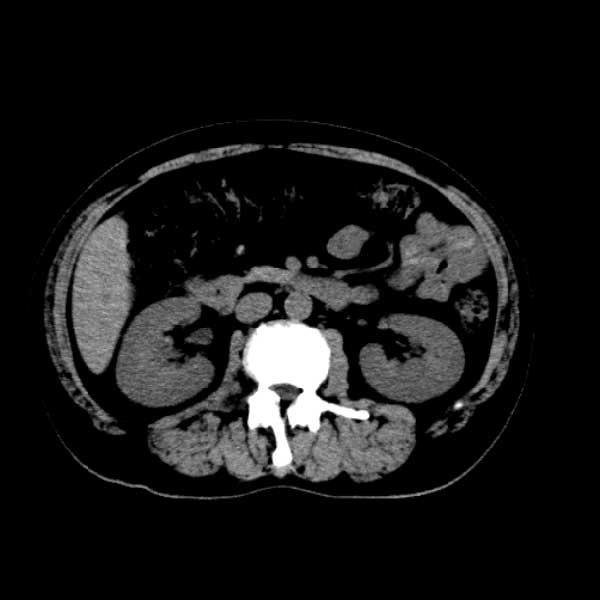

标题: CT13513:男 71 腹部疼痛20余天,近几天高热就诊,骨窗未见异 [打印本页]

标题: CT13513:男 71 腹部疼痛20余天,近几天高热就诊,骨窗未见异

考虑感染性病变可能性大,起源于阑尾?

感染,脓肿形成

考虑为化脓性阑尾炎.脓肿形成.及多肌肉累及.

考虑右侧腰大肌脓肿,向右髂窝、右腹股沟流注。

支持化脓性阑尾炎伴右髂窝脓肿、腰大肌腰方肌脓肿形成。

首先考虑化脓性阑尾炎伴腰大肌、腰方肌脓肿,不除外回盲部结核。

回盲部癌待排除。

患者肠镜检查考虑结肠癌,病理证实

患者肠镜检查考虑结肠癌,病理证实。肺部ct可见多发结节,考虑转移